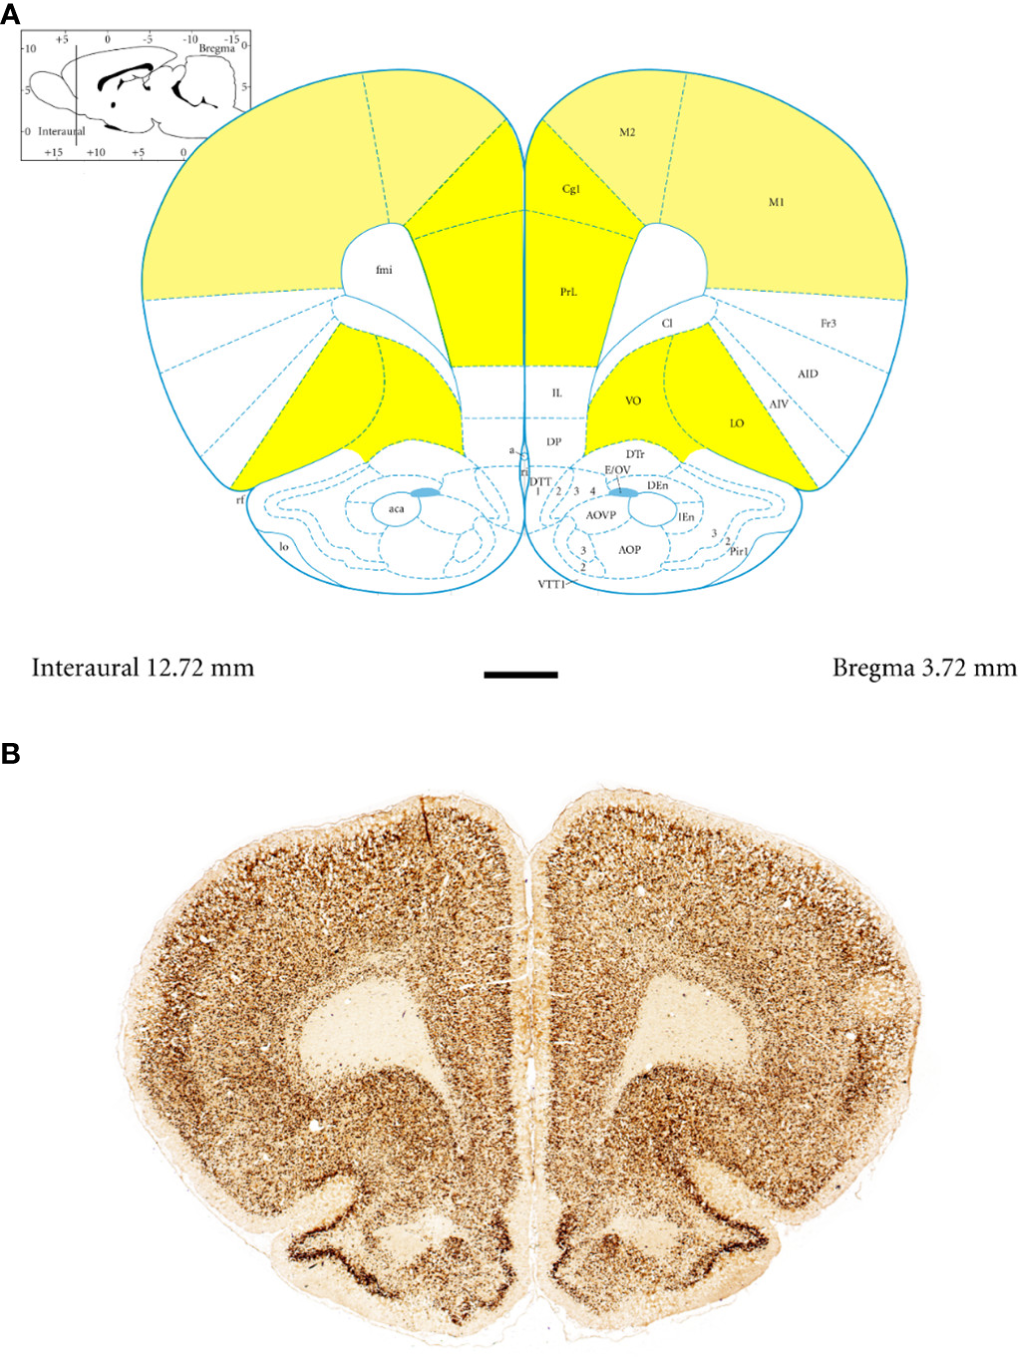

Anatomically, the rat PFC includes two main regions—the medial PFC (mPFC) with the PRL and CG1 and the ventrally located orbitofrontal PFC (oPFC) with the LO and VO—which were chosen for investigation in the present study (Figures 1A, B). In between these regions and dorsally lies the MC, consisting of M1 and M2, which were taken into consideration (Figures 1A, B). In all of these regions, the densities of neurons immunoreactive to PV and/or D2 and fibers expressing TH were evaluated and compared in WKYs and SHRs (Figures 2–13). In addition, as part of preliminary research in these regions, the relationship between PV and D2 was also elucidated (Figure 14).

Figure 1

Topography and subdivisions of the prefrontal cortex (PFC, highlighted in yellow) and the motor cortex (MC, light yellow). (A) Schematic drawing from the rat brain atlas of Paxinos and Watson (69) illustrating the subdivisions of the PFC and MC at the bregma of 3.72 mm. (B) Low-magnification photomicrographs capturing representative coronal sections through the PFC and MC of 5-week-old spontaneously hypertensive rats (SHRs). Key regions include the prelimbic (PRL), cingulate (CG1), lateral orbitofrontal (LO), ventral orbitofrontal (VO), primary motor (M1), and secondary motor (M2) cortices. Scale bar, 1 mm.